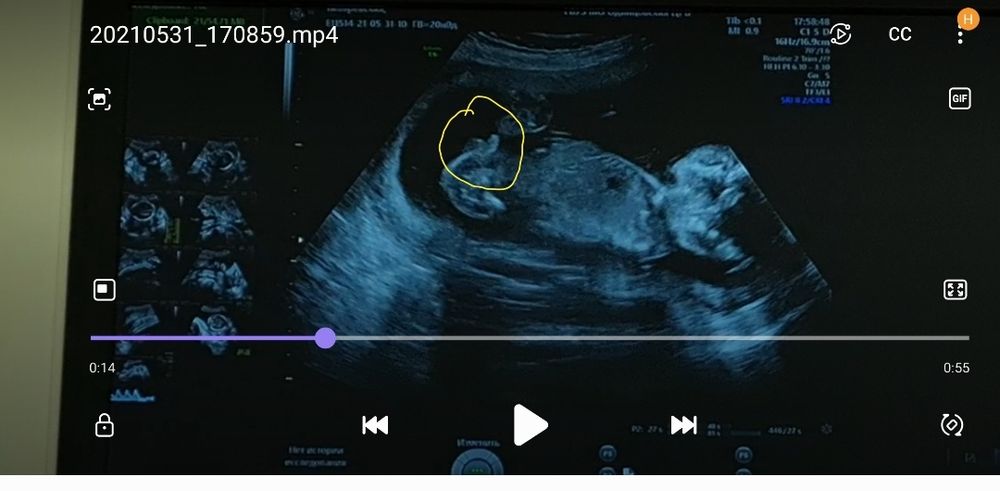

В 20 недель там парней оооочень явно видно))) вот моё узи на втором сурининге

Художница со стажем, не у этого врача. С ней не знакома. Но надо быть прям слепым чтоб такое не увидеть